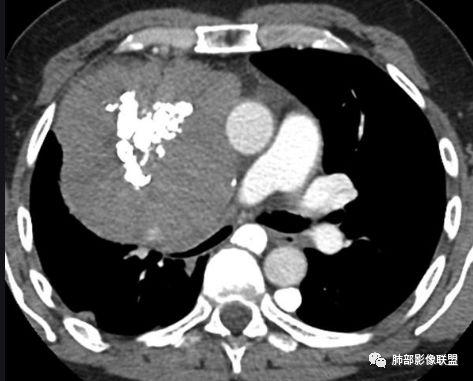

实性部分密度与肌肉类似,钙化粗大、结节状

右侧内乳动脉增粗

实性部分中度强化——增加20~27HU

深分叶,边界尚清,附近未见肿大淋巴结

所以胸腺瘤首选,其次畸胎瘤,SFT

病    理:

胸腺瘤